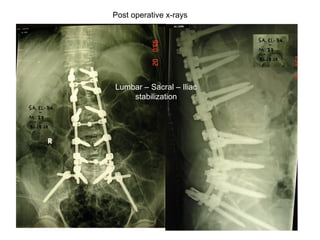

Post operative x-rays

Lumbar – Sacral – Iliac

stabilization